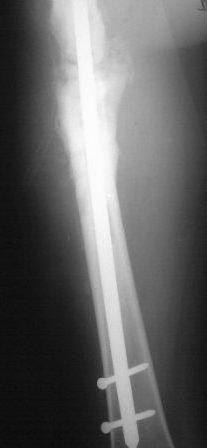

Продолжение случая от 12 января 2009 года.

Представляю контрольные послеоперационные рентгенограммы. Во время операции была

выделена зона перелома небольшим разрезом, произведена декортикация. Окончательный

остеосинтез. Все участникам обуждения большое спасибо за советы и рекомендации.